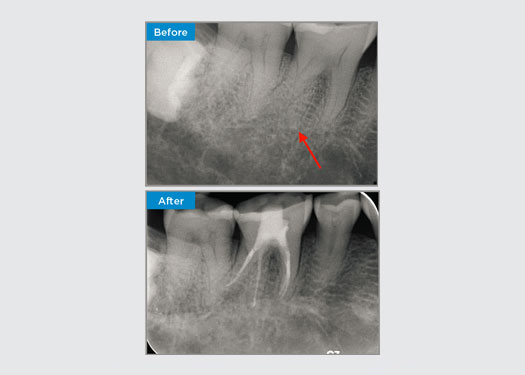

Patiënt presenteerde zich met irreversibele pulpitis op tand 46. Op basis van de preoperatieve röntgenfoto wordt tand 46 gepresenteerd met een extra distale wortel (Radix Entromolaris tandmorfologie). Een CBCT-scan heeft de aanwezigheid van DL-wortel met ernstige wortelkromming bevestigd. Een zorgvuldige bestandsselectie is van cruciaal belang voor deze delicate DB-wortel.

Dr. Jack Lin, endodontist, Sydney, NSW Australië